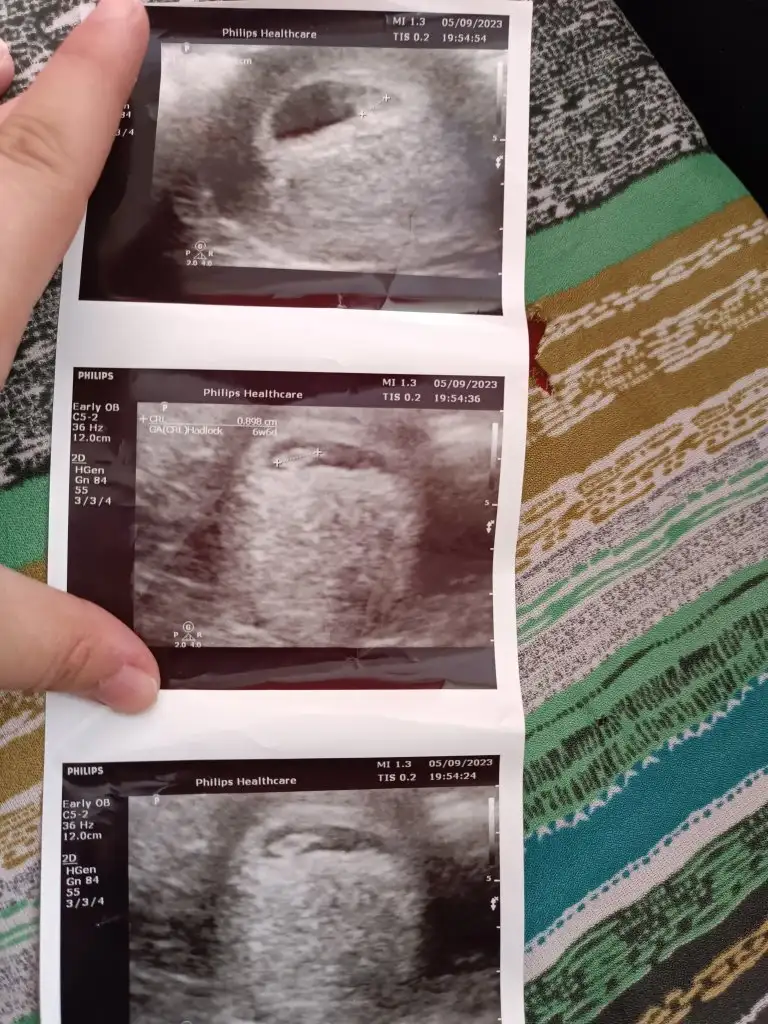

@AnlatilmazYasanir canım benimkine de bakar mısın.üçüncü gebeliğim.6 haftalık karından ultrason.ilk resimde sağda duruyor bebek,sonraki resimlerde solda anlayamadım bende.doktor açısını değiştirmiş herhalde